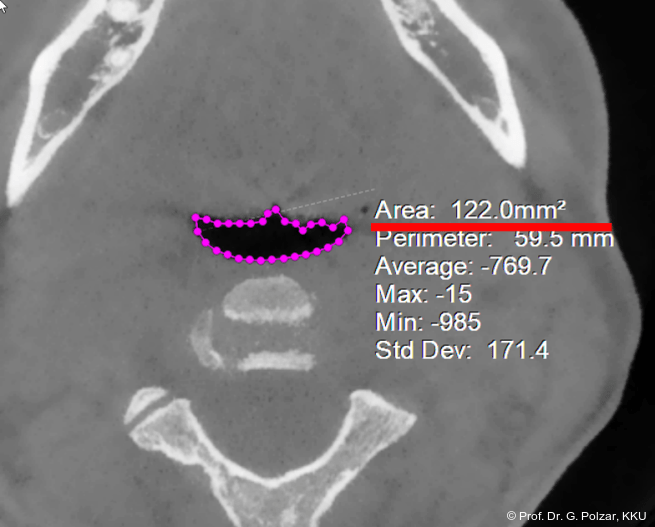

Trotz destruktiver KG-Anatomie mit Peeking, das meint vereinfacht, dass der Kondylus exponiert unter dem Gelenkhöcker liegt, was ein Zeichen für eine ungünstige Gelenkstellung sowie starke Belastung des vorderen Bereichs ist, und verschobener Gelenkscheibe (craniale Kompression) hat sich die Okklusionssituation nach der Behandlung so verbessert, dass die Patientin subjektiv deutlich we­niger Beschwerden hat und sich insgesamt wesentlich wohler fühlt. Der Luftweg hat sich an der engsten Stelle (Isthmus faucium im Bereich der Tonsillen) von 122 qmm auf 202 qmm erweitert (Abb. 15a–d).

Die Atmung hat sich verbessert. Die Patientin bemerkte dies unmittelbar nach der Operation mit den Worten: „Es kommt viel mehr Sauerstoff rein“ und „Beim Joggen kann ich jetzt auch durch die Nase atmen“.

MRT-Untersuchungen des Autors in dem Zeitraum von 2008 bis 2010 ergaben bei eugna­then Bisslagen einen Mittelwert von 139,9 mm an der engsten Stelle des Rachens (Abb. 16). Allein für die Entscheidung, ob sich eine bestimmte Anomalie und deren Therapie positiv, negativ oder gar nicht auf die Atemwege auswirken, sind zahlreiche Kriterien zu berücksich­tigen, die der behandelnde Kieferorthopäde abwägen muss, um dem Patienten die für ihn bestmögliche Therapie zu gewährleisten.